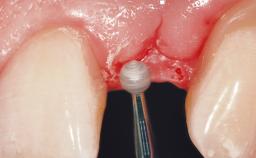

After the placement of three diameter-reduced two-piece implants the bone is augmented with autologous bone chips and DBBM particles to enlarge the crest volume. The surgery is completed with the application of two membrane layers and primary wound closure.